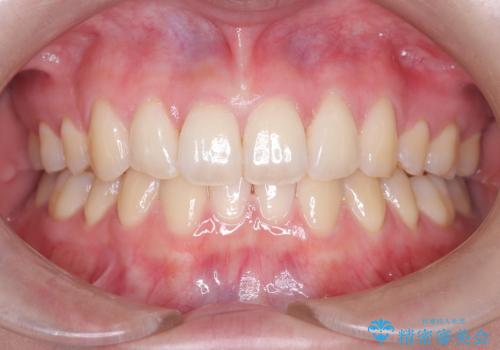

50代女性 八重歯を矯正治療 歯並びの中等度のがたつき

マウスピース矯正が煩わしい ワイヤー装置での非抜歯矯正

担当医 藤巻太一朗